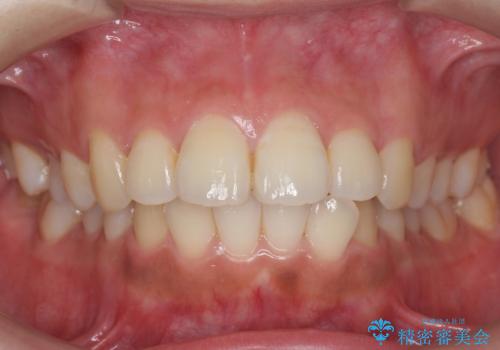

[ 前歯のねじれ・がたつき ] マウスピース矯正

![[ 前歯のねじれ・がたつき ] マウスピース矯正の症例 治療前](https://seimitsushinbi.jp/wp/wp-content/uploads/2024/02/4007c6479f6bce11863dcdd32ed5e39b-500x350.jpg?v=1708502552)

![[ 前歯のねじれ・がたつき ] マウスピース矯正の症例 治療後](https://seimitsushinbi.jp/wp/wp-content/uploads/2024/02/e7a01485e4f4dd0da04705fde4cc34cc-500x350.jpg?v=1708502585)